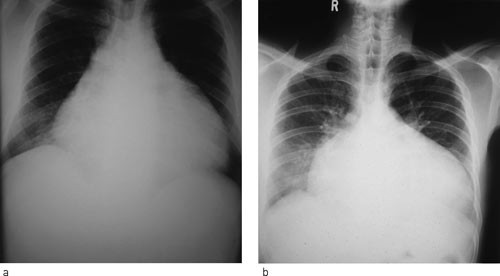

Hivpositiv 41 år gammel mann ble innlagt etter to uker med økende tungpust og ubehag i brystet. Ved undersøkelse var han medtatt, blodtrykk ble målt til 95/65 mm Hg, puls 125/min, respirasjonsrate 44/min. Han hadde ortopné og halsvenestuving. Lungene var klare ved auskultasjon, og det ble påvist hepatomegali uten perifere ødemer. Hjertetonene var fjerne, det var ingen bilyd, og ictus var ikke palpabel. EKG viste sinustakykardi. Røntgen thorax viste uttalt kardiomegali (fig 1a).

De mest aktuelle differensialdiagnosene ble vurdert å være dilaterende/hivassosiert kardiomyopati eller tuberkuløs perikarditt. Røntgen thorax alene er ikke nok til å skille mellom tilstandene (fig 1b). Legen ved lokalsykehuset sto overfor et dilemma: Skulle han satse på diuretika eller gi væske? Diuretika kan være svært uheldig for en pasient med perikardvæske og truende tamponade, som er avhengig av å opprettholde fyllingstrykket. De kliniske tegnene og et normalt EKG gjorde at mistanken om perikardeffusjon var stor.

Pasienten ble overført til regionssykehus. Ekkokardiografi bekreftet en svær perikardeffusjon med fibrintråder typisk for tuberkuløs perikarditt (fig 2), og tegn på hjertetamponade. Det ble gjort perikardiocentese og tappet 750 ml blodig perikardvæske. Tilstanden bedret seg umiddelbart, og pasienten ble på empirisk grunnlag gitt antituberkuløs behandling og prednisolon.

Denne sykehistorien er vanlig i land der hiv og tuberkulose er svært utbredt. Den viser at differensialdiagnostikken ved kardiomegali kan være vanskelig, og at ekkokardiografi, når undersøkelsen er tilgjengelig, ofte er avgjørende for diagnose og behandlingsvalg. Dessverre er tilgangen på kardiologisk ekspertise og ekkokardiografi dårlig eller ikke-eksisterende for store deler av befolkningen i Afrika.